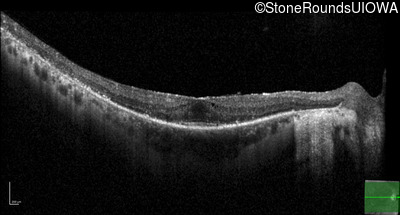

Optical Coherence Tomography - Left - 20/25 sc

Exemplar / OCT Stack

OCT Stack